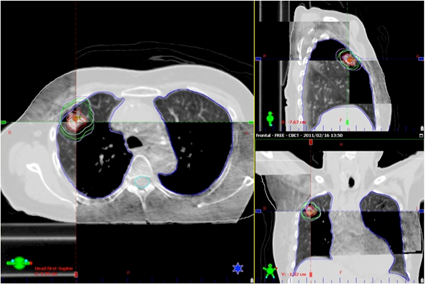

放射線治療計画CT

放射線治療の準備として、まず治療計画を立てるためのCTを撮影します。得られたCT画像から放射線治療医師が、病変や周囲正常組織の位置関係を三次元的に正確に同定し、放射線の投与量と照射範囲を厳密に設定することにより、正常組織の影響を最小限に抑え、かつ病変に集中的に放射線を投与できるように照射方法を決定します。

IGRT

IGRTとは、照射の直前や照射中にX線写真やCT画像を取得して、治療計画時の画像と重ね合わせて、骨やマーカーなどをもとに正確に合わせ込みを行い、位置のずれの量を求めて寝台位置の修正を行ってから照射を行います。